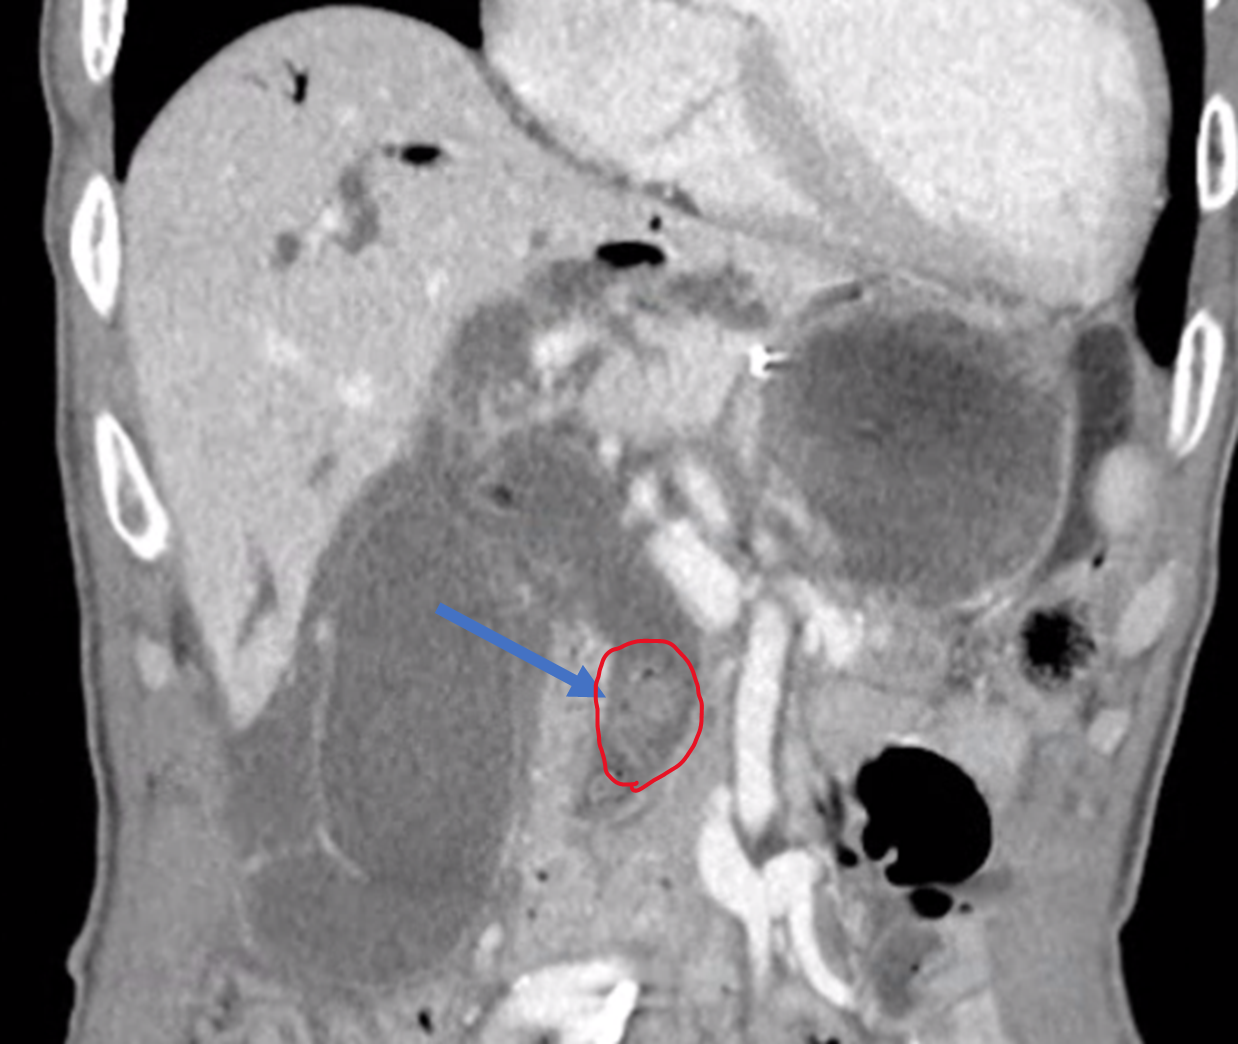

먼저 CT를 촬영해야 하고요.

CT 촬영에서 이 환자에게 이 시술이 정말 필요한 상황인지, 시술 자체에 어려움이나 합병증을 유발할 만한 다른 요인은 없는 지 확인합니다.

위에 제가 올린 CT 처럼 간내담관이 아주 늘어난 경우에는 초음파로도 담관이 잘 보입니다.

이런 돼지 꼬리 모양의 카테터를 넣어 배액관이 잘 빠지지 않게끔 해줍니다. (이름도 돼지 꼬리 입니다.)